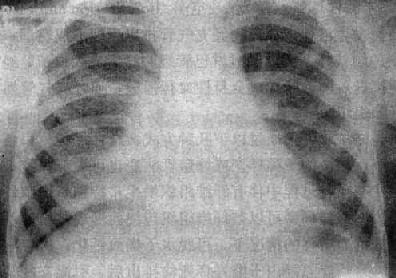

粟粒型肺结核病灶小,透视常难以辩认,故拟诊急性粟型肺结核时应摄片检查。病变早期整个肺野可呈毛玻璃样密度增高。约10日后可出现均匀分布的1.5~2mm大小、密度相同的粟粒状病灶,正常肺纹理常不能显示(图3-1-22)。经过适当治疗后。病灶可在数月内逐渐吸收,偶尔以纤维硬结或钙化而愈合。病变恶化时,可以发生病灶融合,表现为病灶增大,边缘模糊,甚至形成小片状或大片状影,并可干酪样化而形成空洞。

图3-1-22 急性粟粒型肺结核

两肺野布满粟粒状病灶,分布均匀,肺门大